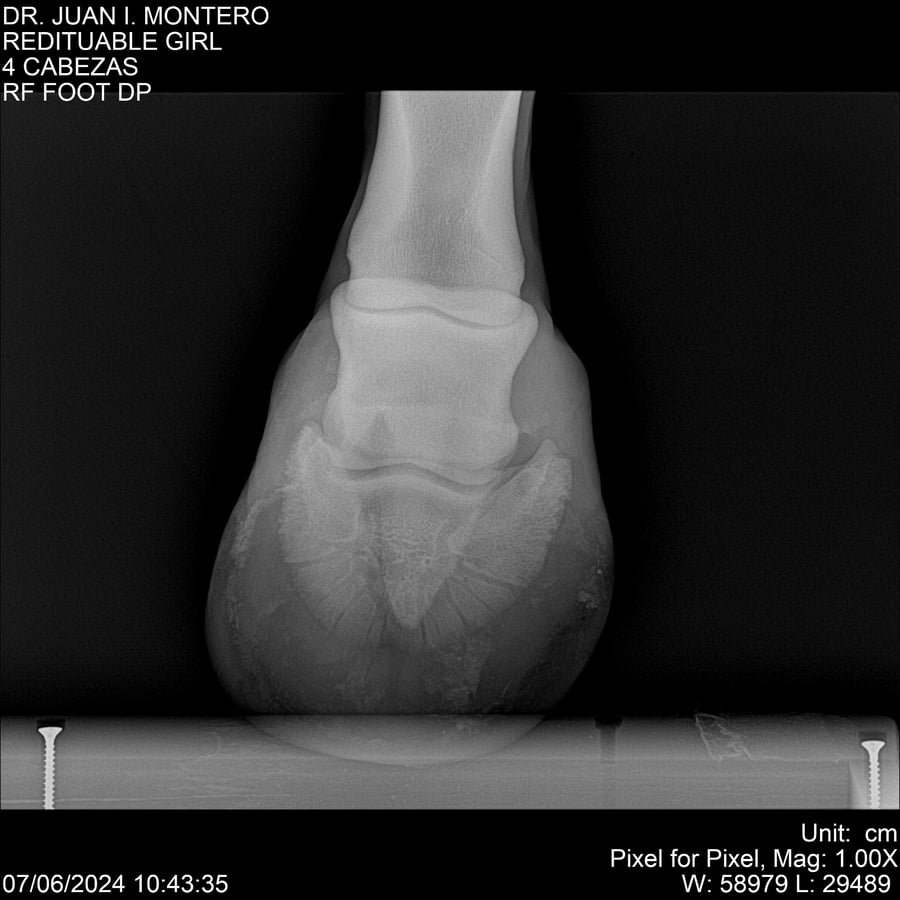

LOTE 19, REDITUABLE GIRL Lote Anterior Volver al remate Lote Siguiente Ficha Contacto Montevideo - Ficha del Lote Identificador: #281096 Categoría: Yeguarizos Montevideo - 79 Visualizaciones ClicData Contacto Empresa: Abelenda N. R., Walter Hugo Nombre*: Teléfono* : E-mail* : Mensaje Enviar Registrese gratis Este contenido Exclusivo está disponible sólo para usuarios registrados Ingresar